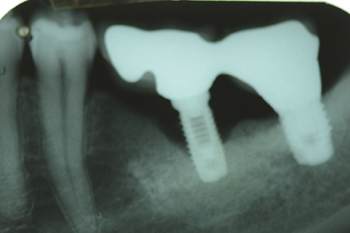

No caso clínico relatado nesta edição, o paciente apresentava sensibilidade à palpação, vermelhidão, edema e fístula na região apical do implante, e aumento progressivo da área radiolúcida apical, três meses após a colocação do implante em função (Figura 1).

A Figura 5 mostra o controle clínico após nove meses. A Figura 6 mostra o controle tomográfico do tecido ósseo neoformado após sete meses.

Figura 1 – Visão panorâmica e corte oblíquo-sagital da região do implante.

Figura 6 – Aspecto do osso apical regenerado após sete meses.